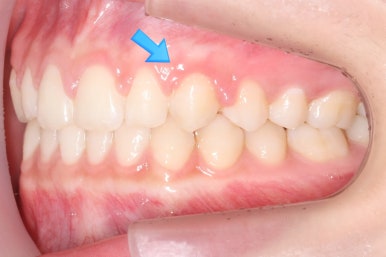

위 사진들은 부산매복치아교정 키다리아저씨치과에 처음 내원하셨을 때의 모습입니다.

화살표 표시한 부분이 바로 영구치 송곳니가 있어야 할 자리인데, 매복이 되어있고 대신 유치가 여전히 남아있는 모습입니다.

환자분의 나이가 만으로 15세였는데, 치과에 처음 올 때 해당 치아가 영구치가 그냥 썩은 줄 알고 오시는 경우가 많습니다.

X-ray를 찍어보고 하면 그 때서야 해당 치아는 유치이며 영구치 송곳니는 뼈 속에 묻혀 있는 것을 알게 되지요.

보통 송곳니는 초등학교 5학년 전후로 나오게 되는데, 이 환자분은 유치가 남아있는 것을 마치 영구치가 나온 것으로 착각하셨던 경우입니다.